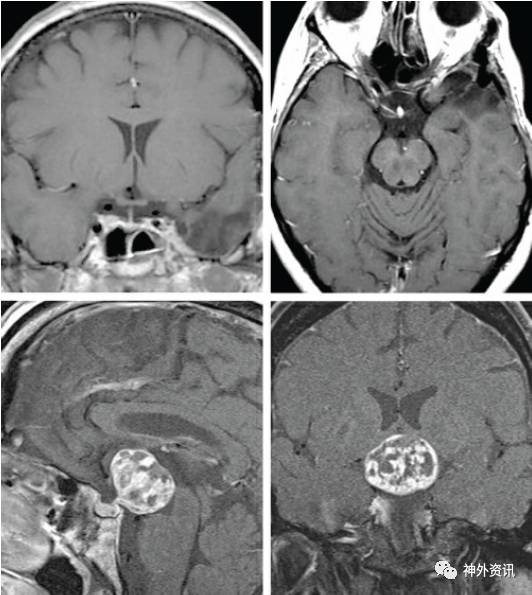

图2:一例巨大的内侧型蝶骨嵴脑膜瘤(上图),经改良眶颧入路完整切除(中图)。该例肿瘤向上显著生长,因此需要通过切除眶顶骨质来获得从下至上的手术视野。同样地,另一例三脑室型颅咽管瘤(下图)也通过相同的入路经终板切除。